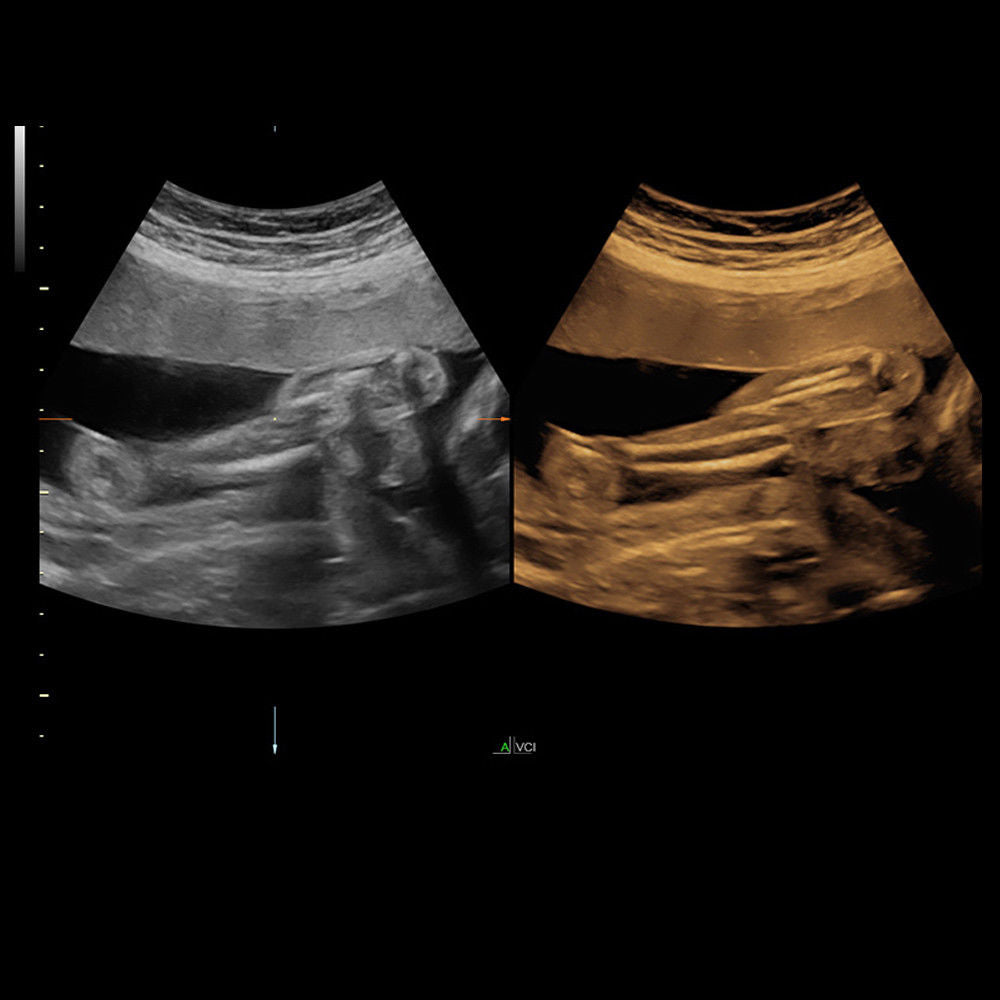

Brand: HD LIVE 4D

MPN: 4DHDLIVE-RAB6-D-SYSTEM-VOLUMETRIC-CONVEX